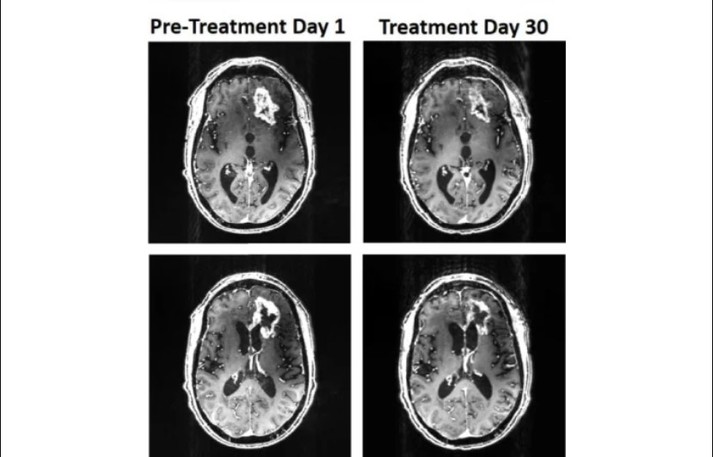

Учені з Х'юстонської методистської лікарні змогли зменшити прогресування ракової пухлини в людини, використавши спеціальний магнітний шолом. Про це інформує ScienceAlert.

«Ми змогли перевірити та підтвердити потенційну ефективність першої неінвазивної терапії гліобластоми у світі», – заявив нейрохірург Девід С. Баскін.

Історія розпочалась з того, що в травні 2018 року 53-річний пацієнт звернувся до лікаря з приводу «зміненого психічного стану». У нього було виявлено велику пухлину. Вже через місяць того ж року пацієнту зробили операцію з видалення гліобластоми, але, на жаль, ракова пухлина продовжувала зростати, а лікування не мало результату.

Традиційні методи лікування не діяли, тому лікарі спробували використати магнітний шолом.

Зазначається, що сам шолом оснащений трьома потужними постійно обертальними магнітами, які генерують коливання магнітного поля. Це поле здатне впливати на людські клітини.

Відомо, що процес лікування був припинений через смерть пацієнта, бо він упав і пошкодив голову.